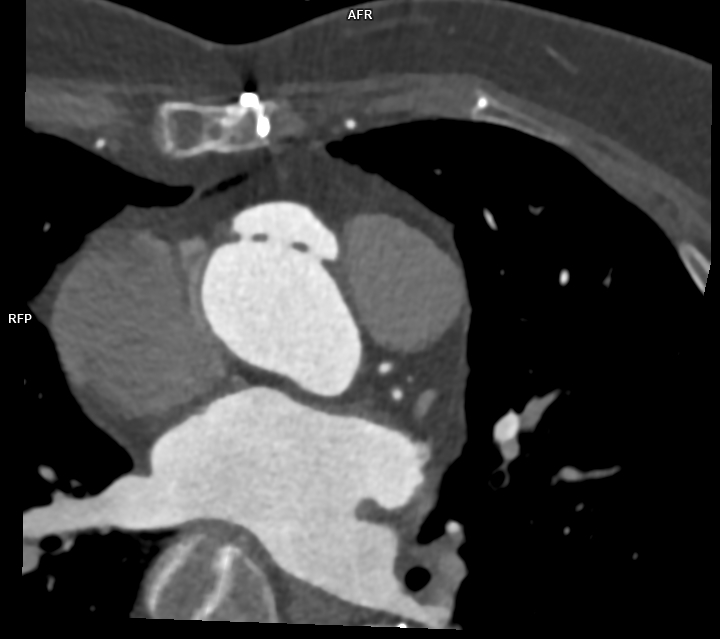

Figura 2: Reconstrucţie în planul perpendicular / ortogonal pe anevrismul format la inserţia inferioară a protezei de aortă ascendentă cu evidenţierea a trei orificii de intrare

Pacient cunoscut cu proteză de aorta ascendentă și proteză endoaortică pentru dilatație anevrismală a aortei ascendente și descendente toracice, efectuează examinare angioCT pentru control postoperator. Se evidențiază câte o dezvoltare anevrismală la inserțiile inferioară și superioară ale protezei de aortă ascendentă și proteză metalică endoaortică de aorta descendentă în poziție normală. Incidental se evidențiază un fald de disecție în segmentul proximal al arterei carotide comune stâng cu ambele lumene circulante.